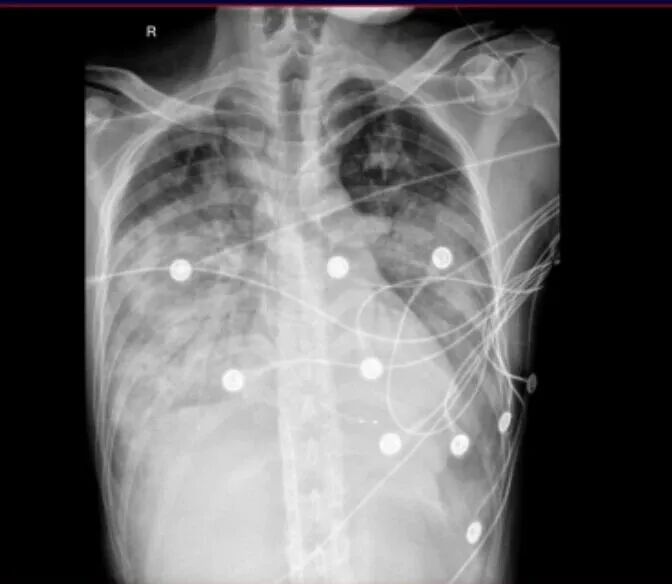

到院后,石聪辉主任带领急诊团队紧急查体,张先生呈端坐呼吸困难状态,虽然对答切题,但讲话断断续续,呼吸急促,口唇已经出现了紫绀(缺氧的典型表现),双肺能听到明显的湿性啰音(提示肺部有积液或炎症),心跳节律不齐。四肢末梢苍白、冰凉,这是休克的早期信号。

情况危急!急诊科立即为他开通无创高流量吸氧,建立抢救通道,同时启动多学科协作(MDT)抢救。多学科专家会诊后,结合张先生的症状和检查结果,判断他病情危重,初步诊断为“重症肺炎、急性心衰、心肌炎”,随即收入重症医学科(ICU)进一步治疗。

进入ICU后,李鑫主任带领重症医学科团队迅速制定抢救方案。考虑到张先生存在严重呼吸、循环衰竭,以及恶性心律失常,乳酸水平持续上升,病情极其危重,有明确行体外膜肺氧合术指针,ICU团队立即实施了清醒心肺支持(清醒ECMO)——简单说就是在患者清醒状态下,用体外膜肺氧合设备替代部分心肺功能,帮他渡过呼吸、循环衰竭的难关;同时植入临时起搏器,纠正他的心律失常问题;还配合了血液净化治疗,清除体内的炎症因子和代谢废物,减轻身体的炎症反应。